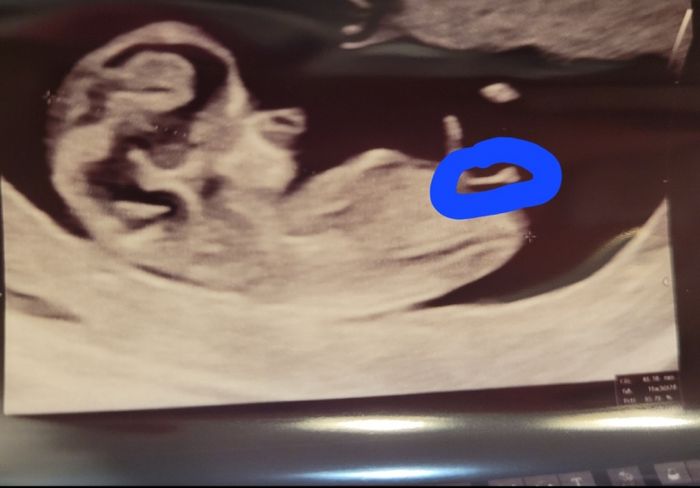

Dici questo? Sono a 10+6 ma poco cambia 🤣🤣 oltretutto datata in base alle dimensioni xk nn ho avuto ciclo sn rimasta incinta allattando🙈

Eh no non è lì il tubercolo, è quello dell’altra foto che si biforca… e la vescica è quell’ovale nero poco sotto. Bisogna incrociare la punta del tubercolo con la vescica, e tracciare la linea della spina dorsale… se l’angolo è maggiore di 35 per la nub è maschio..

però a 10+5 non è molto attendibile anzi! Quindi vediamo che dice il dna

Nub theory, giochiamo un po’ 10

Vedi qui lo vedo bene

Nell’altra non si vede 😅

Comunque non ti fidare del parere del ginecologo perché a me a 10+5 disse maschio… alla tn un altro non si pronunciò ma mi sembrava una palese femmina la mia, e addirittura a 13+5 il primo ginecologo ridisse maschio quando non lo era, e due giorni dopo il dna fetale confermó infatti la mia teoria della femmina. Questo tubercolo punta leggermente in alto, e se lo incrocio con la vescica l’angolo che si forma con la spina dorsale, da questa immagine, mi farebbe dire maschietto. Ma è comunque un’ipotesi azzardata a 11 settimane… i genitali possono essere molto gonfi anche di lato e ingannare! Quindi non ti direi con certezza maschio o femmina, e tra l’altro con una sola immagine. Bisognerebbe valutarlo almeno su due tre immagini… ma tanto hai fatto dna ho letto! Quindi a breve avrai certezza! Tu speri nella femmina avendo già un maschietto?

Il ginecologo diceva femmina ma bohhh🙈🙈 io il tubercolo lo vedo meglio nell altra ecografia 🤣🤣ma in effetti è presto

In realtà il tubercolo si vede meglio in questa che nell’altra.. però a 11 settimane è tanto prestino per pronunciarsi. Bisogna attendere le 12 almeno e il tubercolo può salire fino a 12+5…. Questa foto però inganna eh. Non è proprio piatto piatto quel tubercolo. Se lo incrocio con la vescica a me pare maschietto 😅

Ma è veramente un po’ prestino

Nub theory, giochiamo un po’ 11

Qui si vede meglio pare femmina se nn sbaglio. Il mio primo figlio il tubercolo era proprio tanto all'insù